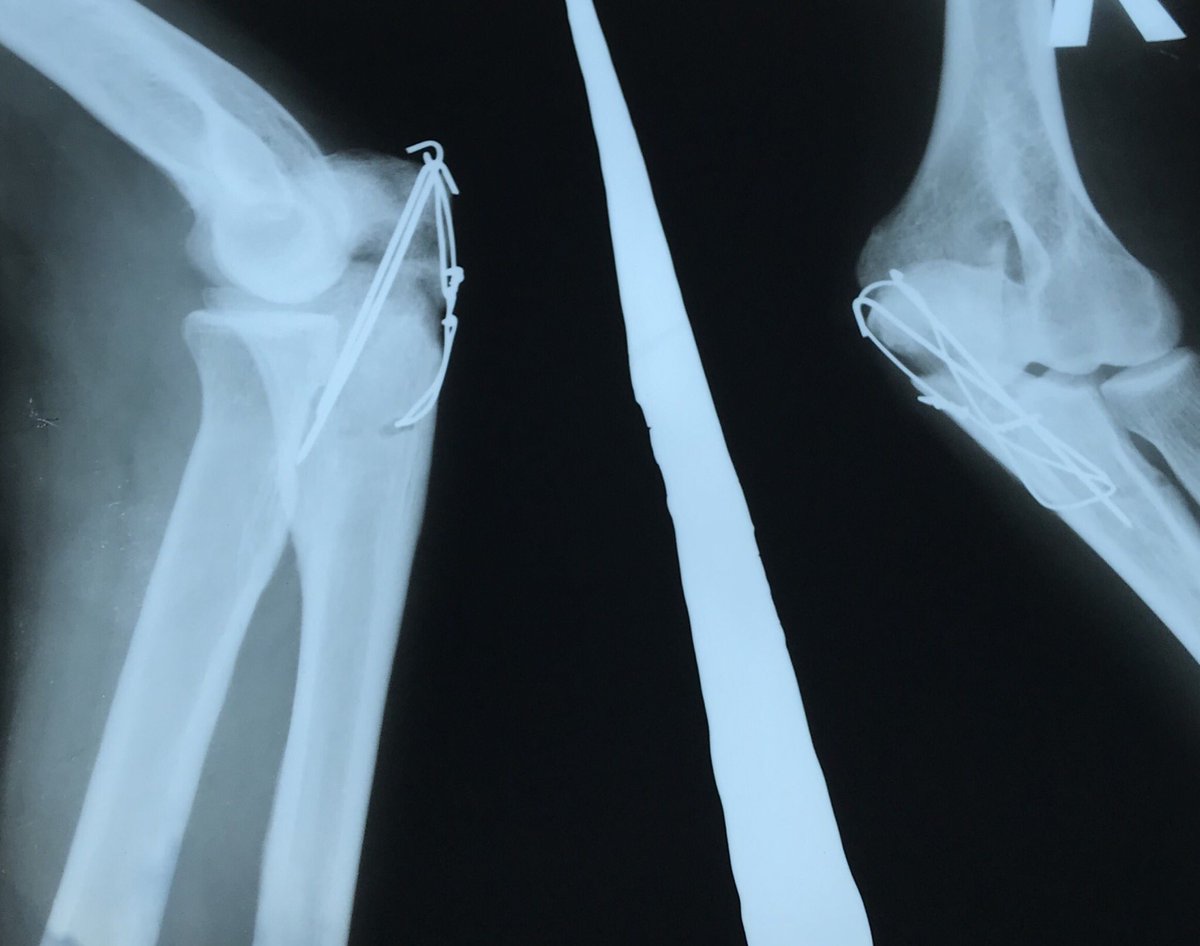

Локтевой перелом форум

Локтевой перелом форум 115 фото